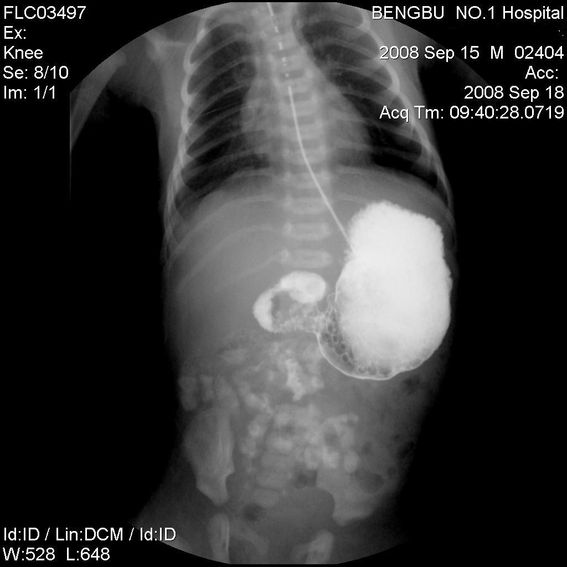

十二指肠降部钡流不能顺利通过,胃及十二指肠球扩张。

考虑----十二指肠降部狭窄-----〔但这几个片子狭窄未能清楚显示,无法判断分型-----膜性或管状〕

考虑----十二指肠降部狭窄

十二指肠降部狭窄(可能为环状胰腺)。

十二指肠降部钡流不能顺利通过,胃及十二指肠球扩张,符合十二指肠降部狭窄